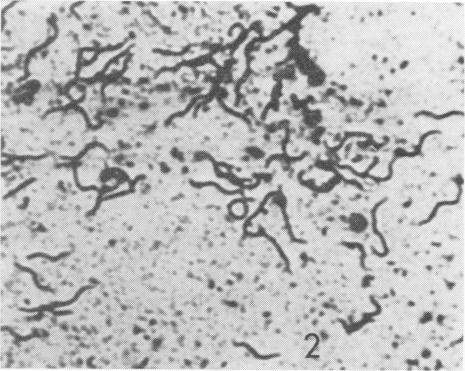

The microscopic examination of colonic scrapings from 12 of 18 normal dogs revealed the presence of a spirochete. From two such dogs a spirochete was isolated and successfully cultured. Although similar in outward appearance to the porcine spirochete of swine dysentery the canine spirochete possessed ultrastructural properties which distinguished it from the porcine agent. This canine agent is thought to constitute a separate species and should not be confused with the agent associated with swine dysentery.

对18只正常犬中的12只进行结肠刮片显微镜检查,发现存在一种螺旋体。从两只这样的犬中分离出螺旋体并成功培养。尽管这种犬螺旋体在外观上与猪痢疾的猪螺旋体相似,但它具有超微结构特性,使其与猪病原体区分开来。这种犬病原体被认为构成一个单独的物种,不应与猪痢疾相关的病原体混淆。